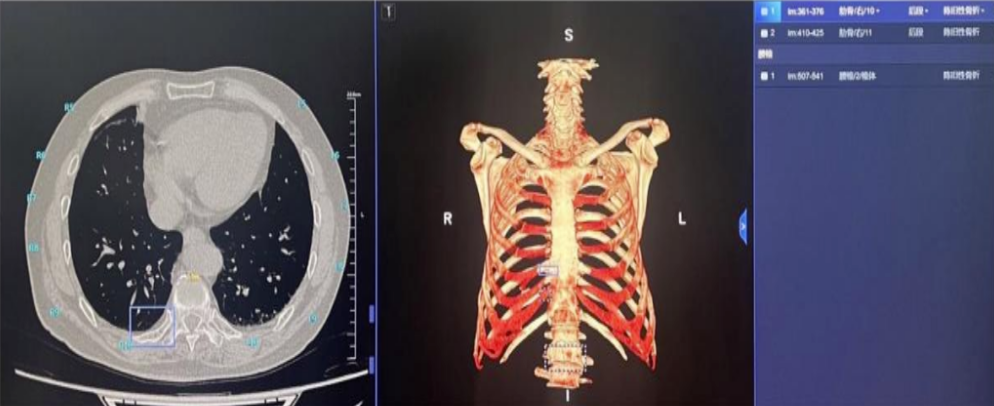

AI骨折辅助检测

对于医生来说,根据CT图像准确地定位骨折位置常常需要花费较多的时间。该模块可以在胸部CT数据基础上,同时对肋骨进行分析,提高肋骨骨折的检出率,尤其是隐匿性骨折的检出率,并对肋骨骨折部位进行精确定位。